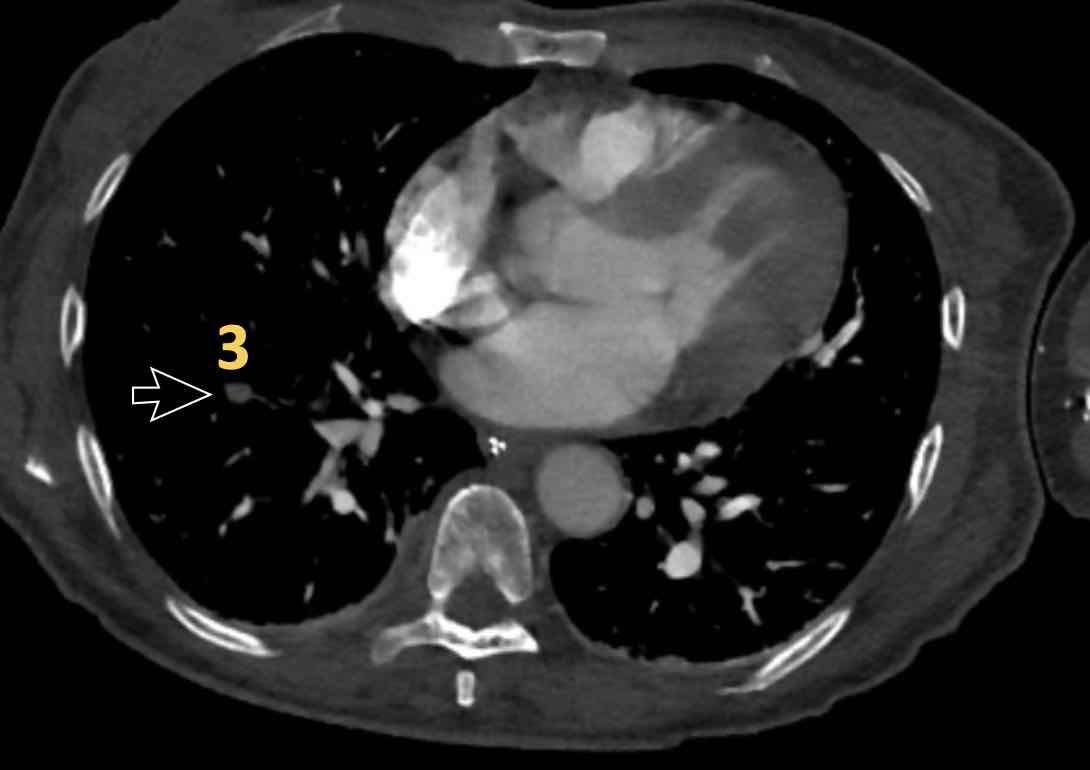

Đây là các hình ảnh của bệnh nhân nữ 59 tuổi tại khoa cấp cứu,

minh họa rõ ràng các huyết khối ở các mức độ khác nhau.

Cuộn qua các hình ảnh.

- Huyết khối trong động mạch thùy đến thùy trên phổi phải.

- Huyết khối tại lỗ vào của động mạch phân thùy đáy sau của thùy dưới phổi phải.

- Huyết khối dưới phân thùy ở phân thùy đáy trước của thùy dưới phổi phải, vài nhánh phía sau động mạch phân thùy.

- Huyết khối tại chỗ phân đôi phân thùy của thùy trên phổi trái.

- Huyết khối tiếp tục lan về phía ngoại vi trong động mạch dưới phân thùy.